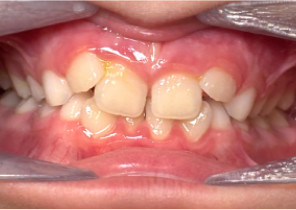

Case Report 2

7 years 11 months old, 24 stages of Invisalign® Palatal Expanders

Courtesy of Dr. David R. Boschken

Pre Invisalign Palatal Expander Expansion

Post Invisalign Palatal Expander Expansion

Post Invisalign Palatal Expander Treatment